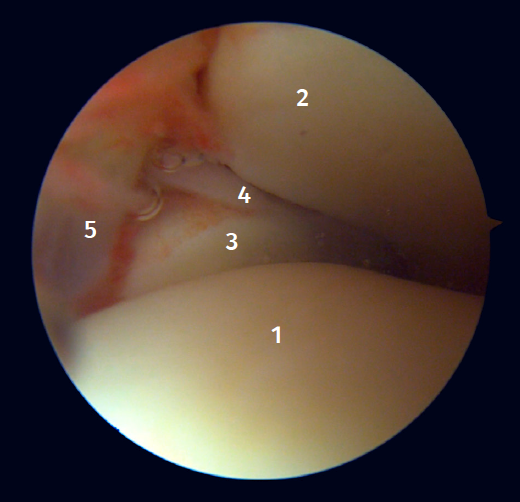

Surgical technique: arthroscopic treatment of acute medial complex injuries

In terms of surgical technique, the working portals are established in the same way as in conventional ankle arthroscopy: one anteromedial portal and one anterolateral portal. We always start with diagnostic arthroscopy to confirm the injury to the deltoid ligament. A probe can be used to verify the laxity of the fibers, and a test can be performed by inserting the probe through the medial groove: the lesion is confirmed if the instrument passes through. For repair, the viewing portal will be the anterolateral portal, thus allowing us to work more directly through the anteromedial portal. The anterior fibers of the superficial tibiotalar and intermediate fibers of the deep portion of the deltoid ligament are the ones that can be repaired with the arthroscopic technique(38). Once the ligament has been identified and dissected, a suture is passed between the fibers using a suture passer. The medial malleolus anchorage zone is prepared with a shaver or a small burr. With the ankle in neutral position, the anchor is inserted while maintaining the tension of the sutures. The intersection of the line parallel to the tibiotalar joint and a perpendicular line marked from the tip of the malleolus and along the lateral border of the malleolus can be used as an anatomical reference for placement(21). After reduction, we again test the fibers for tension and passage of the probe through the medial groove, to confirm adequate repair (Figure 8).